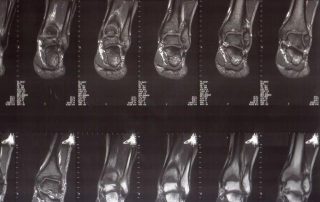

Mężczyzna 21 lat – martwica oddzielająca bloczka kości skokowej

Mężczyzna - 21 lat - leczony z powodu osteochondrosis dissecans ossis talii (martwica oddzielająca bloczka kości skokowej). Leczony przez pięć lat zachowawczo w innym ośrodku. Wykonałem artroskopię, znalazłem 4 ciała wolne chrzęstne oraz 2 fragmenty kostno-chrzęstne.